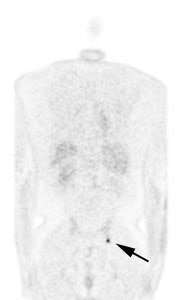

Unsuspected bone metastases: The patient shown below had a left lung non-small cell lung cancer (vaguely seen in the left lung on the PET images shown below). There was no uptake of tracer within the hila or mediastinum to suggest nodal metastases, however, unsuspected bone metastases were found in the right humerus and right hip (black arrows). These findings significantly altered patient management. |

|